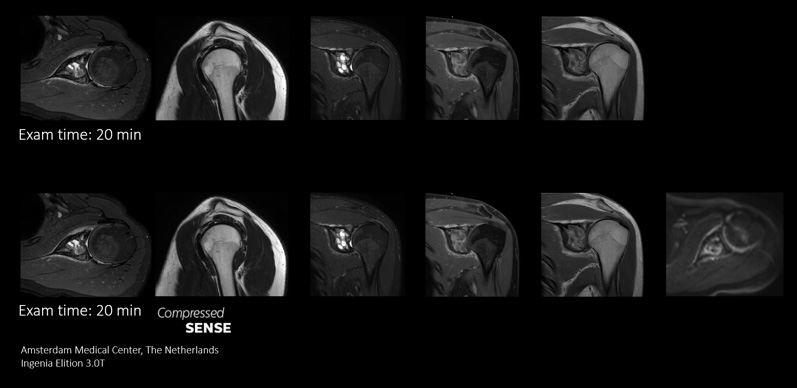

More information in the same time slot

Compressed SENSE gives MRI departments the flexibility to acquire as much relevant information as possible within the MRI scan time slot. Its speeds allows extra routine and functional sequences to be added to enhance diagnostic information.

Add Sequences Scan

This case demonstrates the ability to add additional sequences within the same time slot to enhance your diagnostic confidence. Besides traditional TSE sequences, you can now add a functional DWI sequence within the same timeslot, providing additional information for you to base your diagnosis on.

Because the faster scanning with Compressed SENSE saves us time, we can add a sequence to obtain high quality images for confident diagnosis."

Sachi Fukushima, Radiological Technologist, Kurashiki Central Hospital, Japan